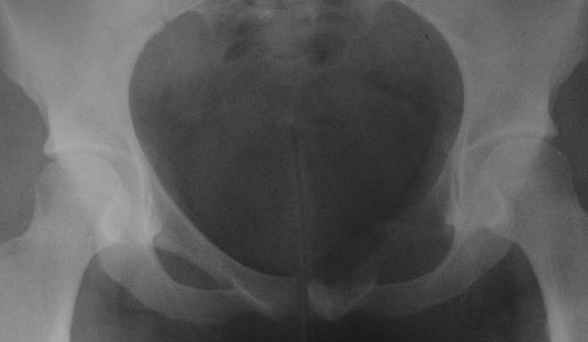

пациентка 20 лет, в сентябре 2005 года почувствовала боли в паху. На снимках заподозрили остеомиелит, лечили антибиотиками без эффекта. К онкологу попала в январе2006. Биопсия в марте 2006 - остеобластокластома. Местные онкологи от операции отказываются.

Вопрос с планом лечения (надо ли замещать деффект и чем) и где оперироваться (опыт подобных операций).В приложении рентгенограммы в динамике (2005 сентябрь, декабрь, 2006 апрель).

Показал случай нашим онкологам. Они советуют сделать КТ, чтобы выяснить распространение процесса в симфизе и вертлужной впадине. Если распространения нет, то у нас обычно просто выполняют резекцию лонной кости без замещения дефекта.